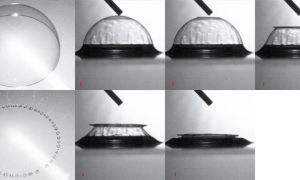

Le premier cœur artificiel fut implanté chez l’Homme en 1969 aux États-Unis. Il a servi de solution temporaire avant une transplantation cardiaque réalisée trois jours plus tard, mais le patient décéda d’infection généralisée peu après. Une question s’imposait alors à tous : si ce cœur artificiel avait maintenu en vie le patient pendant trois jours, pourquoi pas pendant trois mois ? Plus d’un demi-siècle après, les choses ont finalement peu évolué et la mise en place de ces prothèses cardiaques reste exceptionnelle, souvent dans le cadre de protocoles expérimentaux très encadrés et surveillés. L’implantation de ces machines, censées suppléer en totalité la fonction cardiaque, reste donc l’apanage de quelques centres dans le monde.

Nous sommes encore loin d’une technologie maitrisée et adoptée en pratique clinique courante. Beaucoup d’équipes soignantes considèrent encore ces procédures comme un voyage sur la Lune, le patient étant embarqué dans sa fusée tandis que les soignants restés au sol pilotent à distance la procédure depuis la salle de contrôle. Si l’évolution technologique est réelle dans le domaine, la procédure reste un saut dans l’inconnu, un challenge médical, une prouesse réservée à quelques riches pays occidentaux. À l’instar de l’aviation ou de l’aérospatiale, quelques nations s’illustrent dans cette onéreuse recherche médicale, avec une compétition larvée pour aboutir au dispositif idéal. La France et son désormais célèbre cœur artificiel total Carmat1 n’est pas en reste, et l’étude Eficas est actuellement une des rares dans le domaine, avec des résultats attendus dans les prochains mois. Il faut souligner ici l’héroïsme (le mot n’est pas trop faible) de ces rares patients, candidats à une procédure nouvelle, hasardeuse, à haut risque chirurgical et dont l’issue est incertaine. Face à la gravité de leur insuffisance cardiaque avancée et au pronostic si sombre à court terme, à la pénurie de greffons, l’immobilisme scientifique n’est pas une alternative. Il faut avancer, explorer de nouvelles voies, tester des dispositifs, essayer de nouvelles molécules. À côté des progrès en thérapie génique et cellulaire, l’espoir de disposer d’une prothèse mécanique cardiaque est plus que jamais d’actualité. Mais les obstacles au développement de ces machines sont nombreux, et majeurs. Ils sont techniques (ces pompes doivent être biocompatibles, fiables car la panne est mortelle), financiers (il faut lever des sommes considérables pour mettre au point ces dispositifs à haute valeur technologique), mais aussi éthiques. Quelle priorisation donner aux patients pour accéder à la transplantation, quelles conséquences en termes de survie et surtout de qualité de vie ? Ne jouons-nous pas parfois aux apprentis sorciers avec les patients les plus graves ?

Restons optimistes ! Ces précieux patients ouvrent de nouvelles voies, améliorent considérablement nos connaissances, fédèrent les équipes hospitalières autour d’audacieux et attractifs projets médicaux. L’impression 3D, le numérique et l’intelligence artificielle pourraient grandement accélérer la mise en œuvre de ces programmes, pour des patients en attente de greffe cardiaque, voire en alternative à celle-ci. La route est encore longue, mais chaque patient implanté, chaque dispositif explanté, nous rapproche un peu plus de la prothèse cardiaque efficace, fiable et utile. Le cœur artificiel total n’est pas complètement abouti mais bien avancé. Un dernier effort et le mythe deviendra réalité pour de nombreux patients.